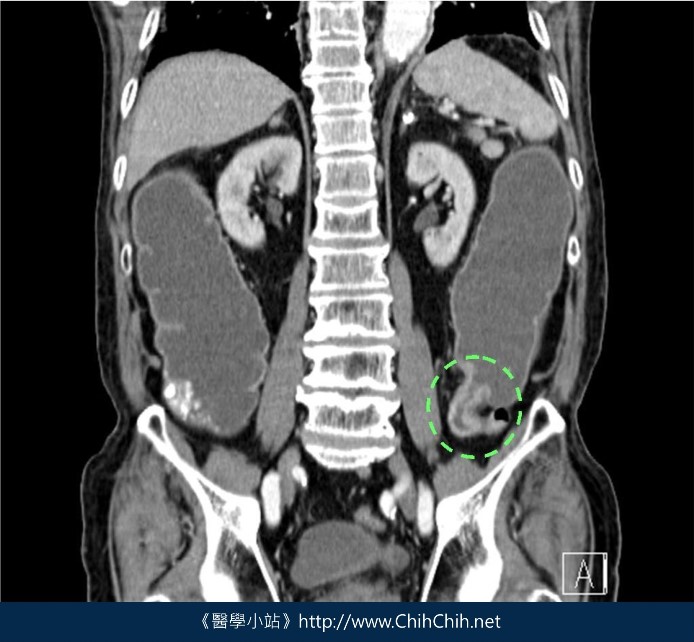

這張圖是由下消化道攝影所發現的大腸癌,原本寬闊、平順的腸道變得狹窄又凹凸不平,看起來就像吃剩的蘋果核。

這種大腸癌便會在影像上出現典型的蘋果核,厚實的腫瘤沿著腸道長成一整圈,使管徑變小,固態糞便就不容易通過。患者的排便習慣可能變得很紊亂,時而便秘,時而拉稀。